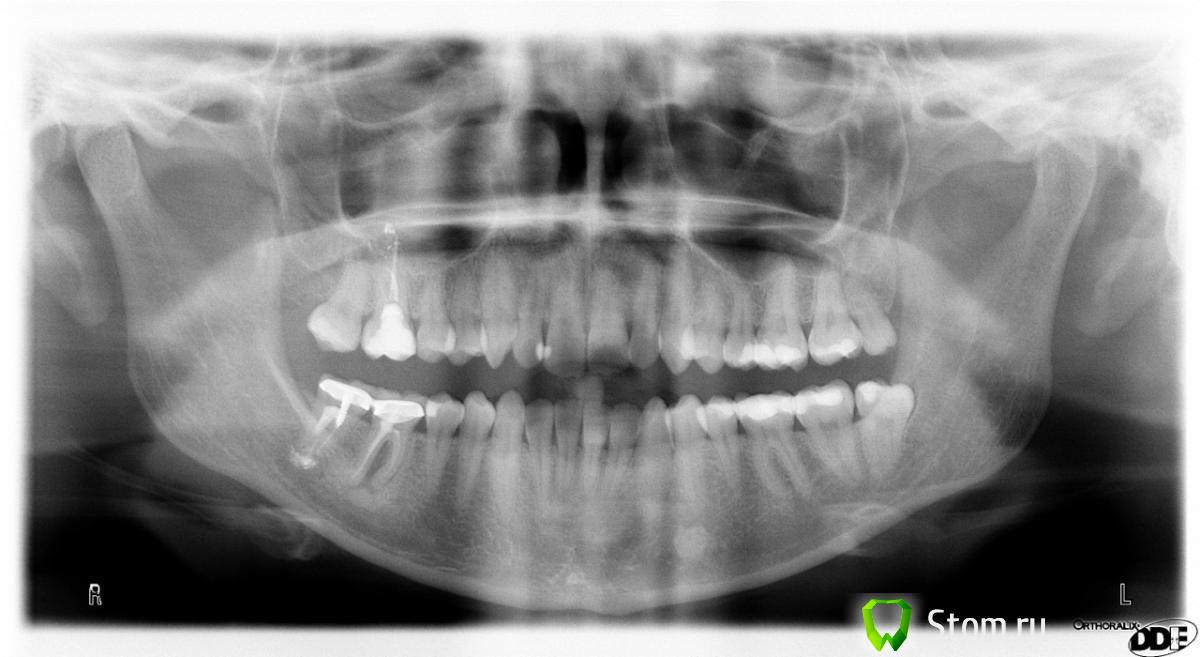

amys Опубликовано 20 января, 2013 Автор Поделиться Опубликовано 20 января, 2013 ЗДравствуйте еще раз! Прошло полгода, зуб вылечили, киста почти ушла. Снимок прилагаю.Сейчас на зубе стоит временная коронка. Есть проблемы с челюстным суставом - он болит при открывании рта, рот широко не открывается, при движении челюсти в суставе будто скребет песок. Пошла на консультацию к гнатологу - мне сказали лечить 7ку справа снизу, удалять 8ки и ставить брекеты, и только потом ставить постоянные коронки. При этом уверенности в успешном вылечивании 7ки я не увидела. Возможно ли вылечить 7ку? Сложно ли будет удалить 8ку снизу слева? (это будет операция с распиливанием и наложением швов?) Неужели брекеты - это единственный выход? Ссылка на комментарий

IvanK Опубликовано 20 января, 2013 Поделиться Опубликовано 20 января, 2013 ЗДравствуйте еще раз! Прошло полгода, зуб вылечили, киста почти ушла. Снимок прилагаю.Сейчас на зубе стоит временная коронка. Есть проблемы с челюстным суставом - он болит при открывании рта, рот широко не открывается, при движении челюсти в суставе будто скребет песок. Пошла на консультацию к гнатологу - мне сказали лечить 7ку справа снизу, удалять 8ки и ставить брекеты, и только потом ставить постоянные коронки. При этом уверенности в успешном вылечивании 7ки я не увидела.Возможно ли вылечить 7ку? Сложно ли будет удалить 8ку снизу слева? (это будет операция с распиливанием и наложением швов?) Неужели брекеты - это единственный выход?По лечению - промолчу.Удаление - ищите Доктора, для которого такое удаление стандартное-повседневное. Создайте тему в ортодонтическом разделе Ссылка на комментарий